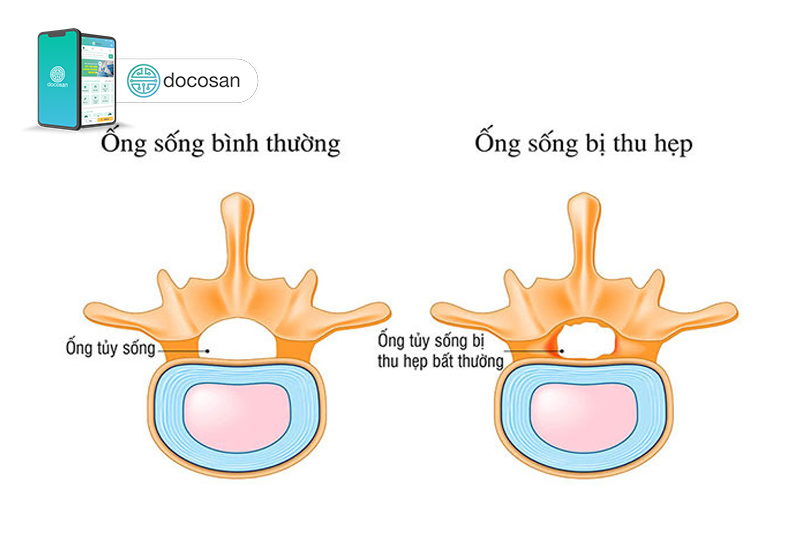

Hẹp ống sống

Ống sống là một khoang rỗng của đốt sống, trong đó có tủy sống và các rễ thần kinh.

Nếu ống sống bị hẹp sẽ chèn ép, đè lên các rễ tủy sống và các rễ thần kinh tương ứng gây ra đau lưng, đau dây thần kinh hông to và cảm giác tê tay chân khó chịu cho người bệnh.